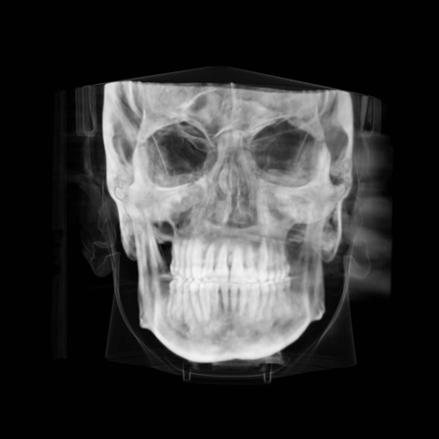

Clinical evaluation showed a mild Class III skeletal pattern with a constricted maxilla, mildly dolichofacial and straight

profile (Figure 1). Full adult dentition was present with all third molars extracted. Maxillary and mandibular incisors were normoclined. The maxillary midline coincided with the facial midline, and the mandibular midline was 2 mm to the right of the facial midline. There was a 2 mm to 5 mm lateral open bite on the right side from the second molar to the lateral incisor, and the maxillary occlusal plane was canted to the left of the interpupillary line. A lateral tongue thrust into the open bite was noted on swallow.

The right side was in posterior crossbite and there was an edge-to-edge anterior bite with wear on the maxillary central incisors. Mild gingival recession was noted, but soft tissue was generally within normal limits. CBCT analysis found no radiographic evidence of osteoarthritis in the TMJ joints, nor osseous or apical pathology involving the maxillary or mandibular teeth. His airway was not constricted. Initial report from the myofunctional therapist indicated that the patient never developed a mature swallow sequence and had a bilateral posterior tongue thrust.

Figure 1. Initial records.